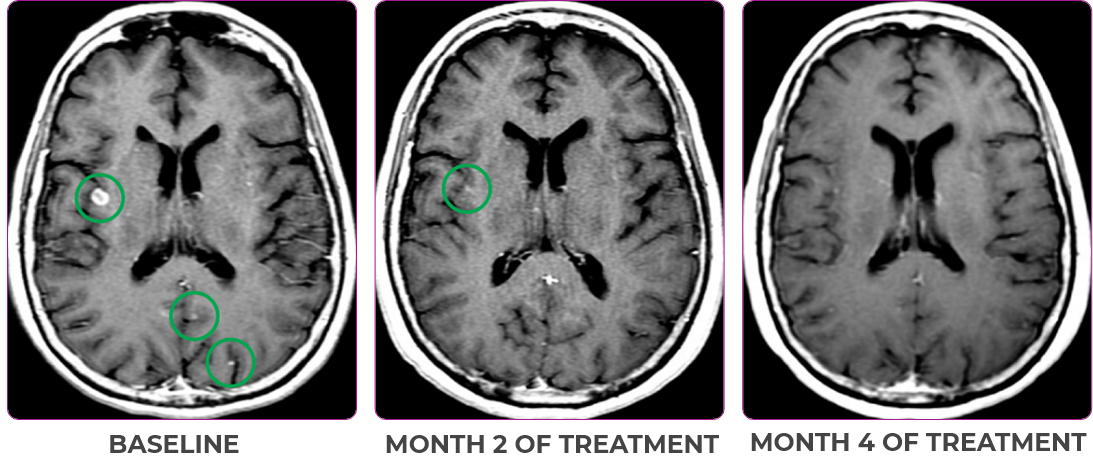

Response in primary and metastatic lesions1

MRIa imagery of the brain. Green circles indicate baseline brain metastases.1

SCAN 2: BRAIN

aMRI, magnetic resonance imaging.